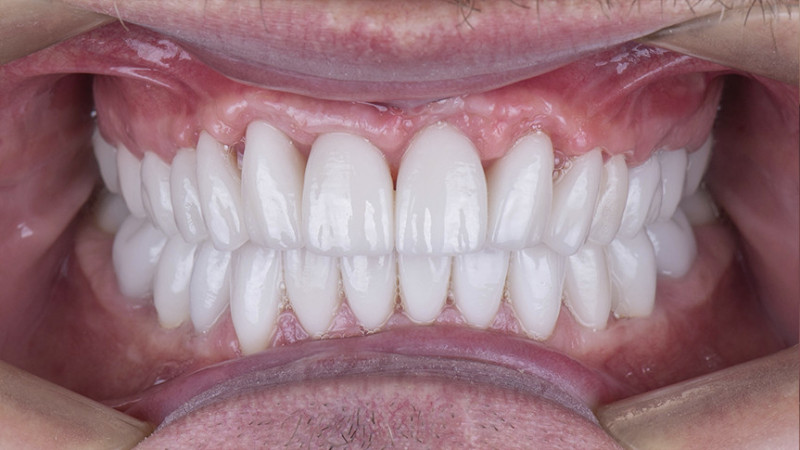

Установка коронки на зуб

Провели швейцарскую профгигиену. Перелечили зубы с несостоятельными пломбами и воспалениями. Удалили зубы в боковом отделе с одномоментной имплантацией и пластикой десны. Установили временные коронки. После приживления имплантатов установили постоянные коронки из диоксида циркония на зубной ряд нижней и верхней челюсти.